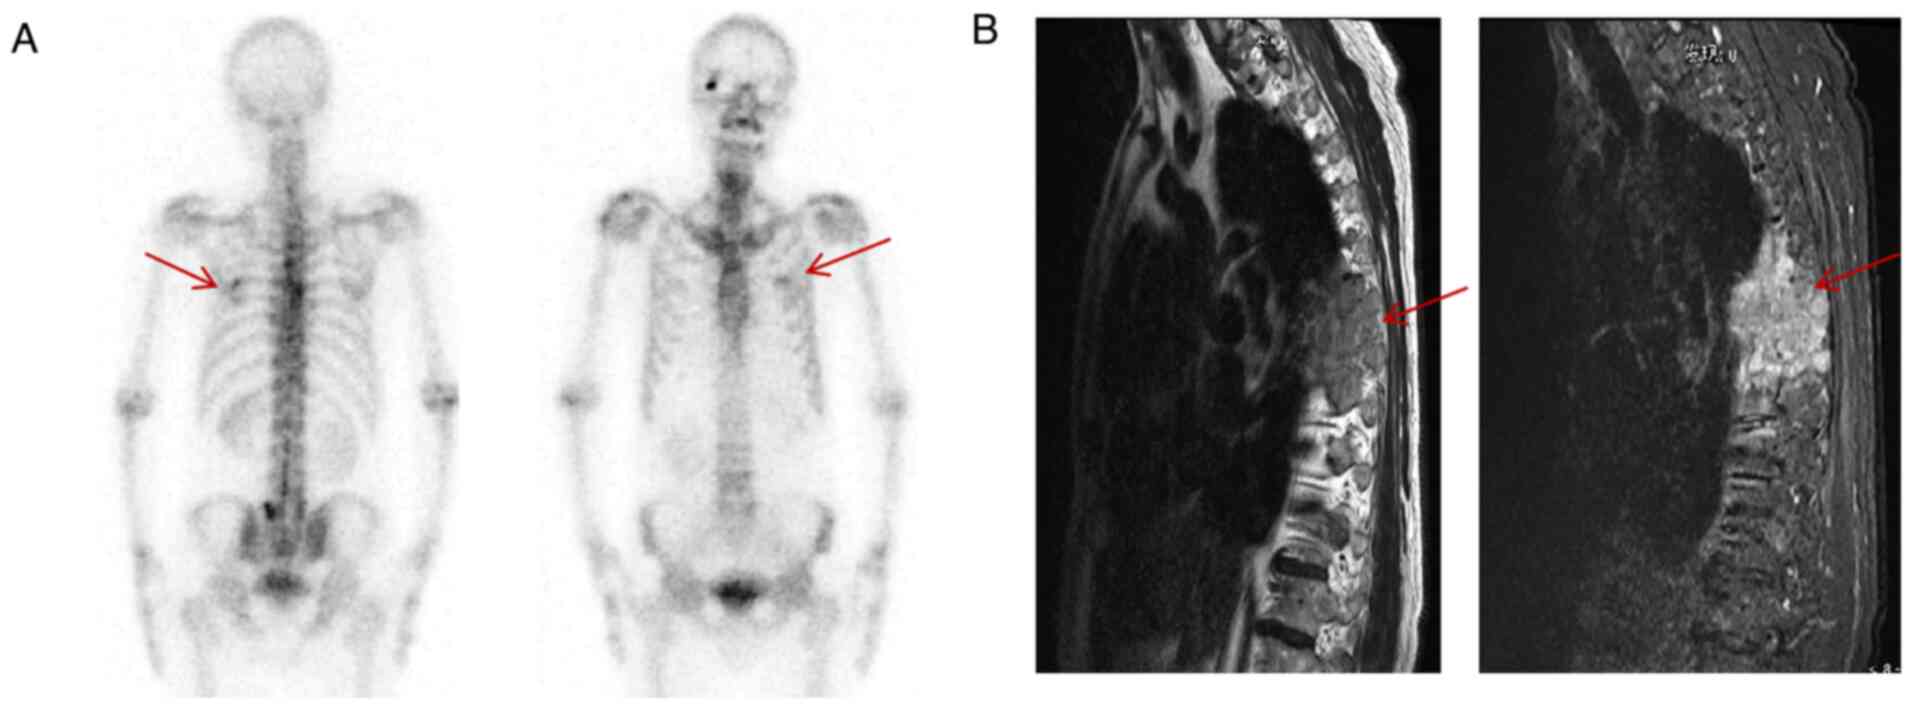

Kartagener syndrome combined with small cell lung cancer: A case report and literature review

Kartagener syndrome (KS) is a rare autosomal recessive genetic disease characterized by visceral inversion, sinusitis and bronchiectasis. Small‑cell lung cancer, a common tumor with poor prognosis, rarely coexists with KS. The lack of typical clinical symptoms can lead to missed or incorrect diagnoses, and to date, only few cases of this combination have been reported. The current study presents a case of KS with small cell lung cancer that was promptly diagnosed and treated at Jining No. 1 People's Hospital (Jining, China). Sharing this case may contribute to the advancement of respiratory medicine and aid doctors in the diagnosis and management of similar conditions.

Figure 2